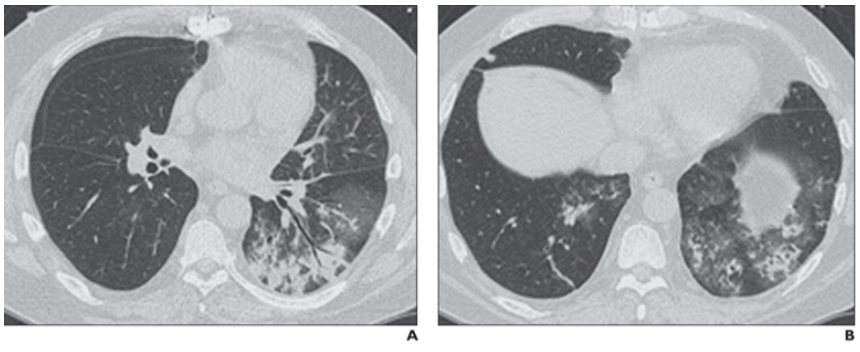

PIV肺炎与其他病原体感染的临床表现不易区分。咳嗽、流涕及咽痛是最常见的症状,特殊表现为犬吠样咳嗽,喘息更常见(86%)。原基础病急性加重也是常见表现(如哮喘、慢阻肺及心衰)。查体哮鸣音比例高(52%),氧疗、插管率及入ICU比例与其他肺炎无显著差别。PIV肺炎住院天数相对较少。PIV肺炎的影像学表现无特异性,与其他病毒性肺炎的表现相似,包括树芽征、间质浸润、磨玻璃影、支气管壁增厚和支气管周围实变。美国一项多中心回顾性门诊调查研究中分析了24例成人PIV感染患者(免疫功能低下占38%)的影像特点【这些患者没有检测到其他病原体,7天内有胸部CT结果】:以气道为中心的分布(67%)【气道中心分布患者例数除以24,但这24例患者中有4例没有肺部感染表现。但个人认为应该用气道中心分布患者例数除以20,结果所得比率为80%】,树芽征(54%)、支气管壁增厚(支气管炎、细支气管炎、支气管肺炎)(图1,图2)显著高于流感病毒(27%)、腺病毒(10%);与呼吸道合胞病毒(53%)相仿(类似的分子结构:副黏病毒科,负单链RNA病毒)。磨玻璃病变(38%)、多灶性实变(25%)(图3)与其他病毒肺炎无明显差别(除外腺病毒),无双肺弥漫性磨玻璃或实变病例,无肺炎比例17%,显著低于流感病毒(43%)。由于绝大多数门诊PIV感染患者症状很轻, 可能完全没有做CT检查, 因此该研究结果仍值得商榷。图1. 一例61岁女性患者,新发呼吸困难所致副流感病毒引起的支气管炎。CT图像显示支气管壁弥漫性增厚。

图3. 一例接受双侧肺移植的54岁男性副流感病毒引起的多灶性肺炎。CT图像可见双下肺叶有实变和磨玻璃样变。

图源:AJR Am J Roentgenol, 2013, 201(3):550-554.另有研究总结了6例造血干细胞移植患者影像学特点,代表免疫受损严重患者的影像特点,其中多发小结节(最常见)(<5 mm为主,也有5~10 mm结节或>1 cm结节),支气管周围分布,外周分布的磨玻璃密度增高影、含支气管充气征的实变(1/2出现)(图4)。